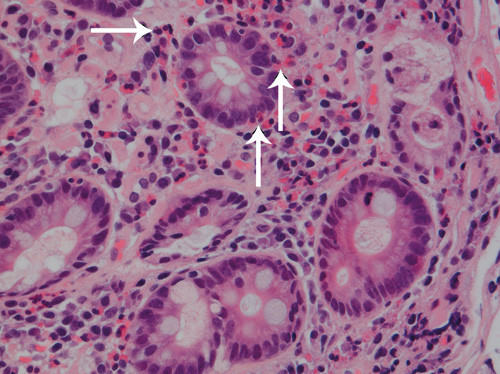

Ved oppfølgende enteroskopi fant man fortsatt noe ventrikkelretensjon. Slimhinnene i antrum, duodenum og øvre del av jejunum var lett betente (fig 2), men forandringene var relativt beskjedne sett i lys av sykdomsbildet. Histologiske prøver av endoskopiske biopsier fra tynntarm (fig 3) viste infiltrasjon av eosinofile granulocytter med opp mot 50 celler per synsfelt, vesentlig i lamina propria, forenlig med eosinofil gastroenteritt.

Histologisk finnes normalt eosinofile granulocytter i lamina propria i hele gastrointestinaltractus unntatt i oesophagus, og det har derfor vært usikkerhet om hva som kan kalles en reell økning i antall. Det finnes ingen konsensus for de histologiske kriteriene for eosinofili i mage-tarm-kanalen, men man har foreslått minst 20 eosinofile granulocytter per synsfelt (400x forstørrelse) som grenseverdi (cut off) (7, 15). Dette vil imidlertid bare gjelde i ventrikkel og proksimale deler av tynntarmen da det normalt kan finnes høyere antall eosinofile granulocytter i distale ileum og proksimale colon (19). Andre faktorer som lokalisasjon av eosinofile granulocytter i tarmveggen og fravær av annen patologisk forandring (for eksempel vaskulitt) må vurderes. Man må også være oppmerksom på at forandringene kan være fokale, så det er viktig med flere biopsier ved endoskopi (7, 12, 20). Vi tar minst fem biopsier fra antrum og fem fra duodenum ved gastroskopi når det er mistanke om eosinofil gastroenteritt (14). I tillegg utføres enteroskopi ved behov.